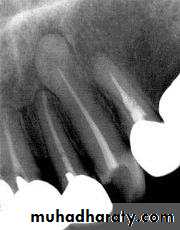

HYPERCEMENTOSIS

• Is an abnormal thickening of cementum.

• May affect all teeth of the dentition, be confined to a single tooth, or even affect only parts of one tooth.

• If the overgrowth improves the functional qualities of the cementum, it is termed cementum hypertrophy.

• If the overgrowth occurs in non-functional teeth or if it is not correlated with increased function, its termed hyperplasia.

Extensive hyperplasia of cementum is occasionally associated with chronic periapical inflammation.

Hyperplasia of cementum in non-functioning teeth is characterized by a reduction in the number of Sharpey’s fibers embedded in the root.

This may cause problems during tooth extraction.

Hypercementosis affecting all the teeth may be associated with Paget’s disease.44